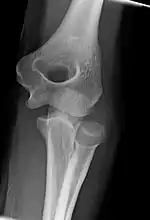

Left elbow extended and flexed

Normal radiograph; right picture of the straightened arm shows the carrying angle of the elbow

When the arm is extended, with the palm facing forward or up, the bones of the upper arm (humerus) and forearm (radius and ulna) are not perfectly aligned. The deviation from a straight line occurs in the direction of the thumb, and is referred to as the "carrying angle".[22]